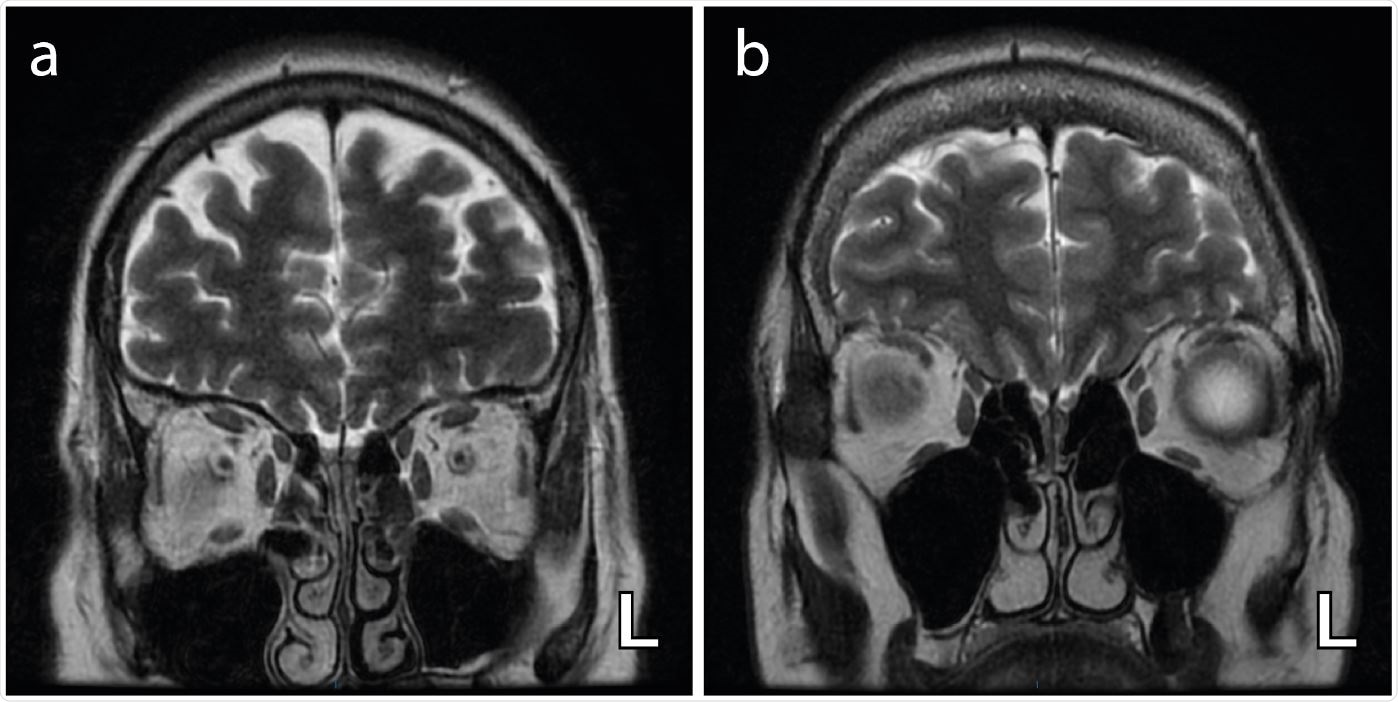

Axial T2-weighted coronal images demonstrating bilateral and complete obliteration of the olfactory clefts (a) with no associated olfactory bulb asymmetry and (b) with asymmetry of the olfactory bulbs (left (L) bulb relatively enlarged)

The study results showed bilateral blocking of the olfactory cleft in 6 patients and subtle olfactory bulb asymmetry in 3 patients. No abnormalities in the MRI signal downstream of the olfactory tract was noted. Heterogeneous abnormalities (decrease or increase) were observed in glucose metabolism in core olfactory and high-order neocortical areas. The team found a correlation between regional cerebral glucose metabolism and the severity and duration of COVID-19-related loss of smell.